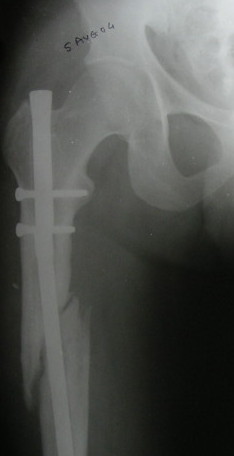

Failure to close 4/4 cortices 6 months post-op definitely meets definition criteria of non-union. Obviously, fixation has failed in this case and needs to be achieved via exchange nail.

Tough to tell from these x-rays, but fx ends appear sclerotic with bridging callus partially present - likely hypertrophic non-union, but you can do a bone scan to confirm viability.

VMI> Kindly note. a) the nail is going towards the medial aspect

VMI> of the lower end thus causing a 5* varus at the # site. b) there

VMI> is a slight overiding causing a centimeter of shortening.

Such slight defomation must be possible to correct acutely using a distractor.

VMI> Implant removal may not be easy with the distal screw broken and

VMI> the nail broken too.

Exactly. We removed recently such a distal part of a hollow nail using a guide pin inserted from the knee through the stab wound. The hole in the notch was made by a cannulated awl. Then the pin passed to the proximal end of the femur, and a cannulated nail inserted to push the broken part distally over the guide pin. There is a set for broken

nail removal.

It is agreed by almost all that this is a hypertrophic nonunion.

It has been proved beyond any doubt by experience and literature that hypertrophic nonunion does not need bone grafting but only stabilisation. That is because the reason for NU in this case is instability. This stabilisation can done by 1) rigid plate fixation , 2) ring fixator, by itself or with distraction. (GSK et al), or 3) by thick nail properly locked above and below. I have not done bone grafting for such a nonunion in the last 25 years and have not regretted. So bone grafting, as an additional safeguard measure, is not essential except to protect yourself at the consumer court. (Marco, Bhayendra, Sunil, Abhay, Yasir and Sanjay) The second point is : Is there sufficient amount of angulation and overriding that the the fracture needs to be realigned? If the answer is yes, then only the question of doing it by distraction (Alex) or by opening disengaging the fracture and realigning (Abhay, Yasir and Sanjay)

Remove the implant. (taking all sort of precautions and preparations). The fracture will not disengage or disimpact. Introduce a beaded guide wire. While entering the distal fragment, I will try to guide it more laterally (and not in the same earlier track) by using one or two Poller screws (pins) to be in the center of the medullary cavity, ream up to 12mm or more if possible, introduce an Indian ss nail (of which I am confident) size 1 mm less than what I have reamed, and lock with one proximal and 2 distal bolts. This nail if it has entered properly the way it was meant to be some correction of the angulation would have taken place. Weight bearing as soon as the patient can. Wish me all luck.